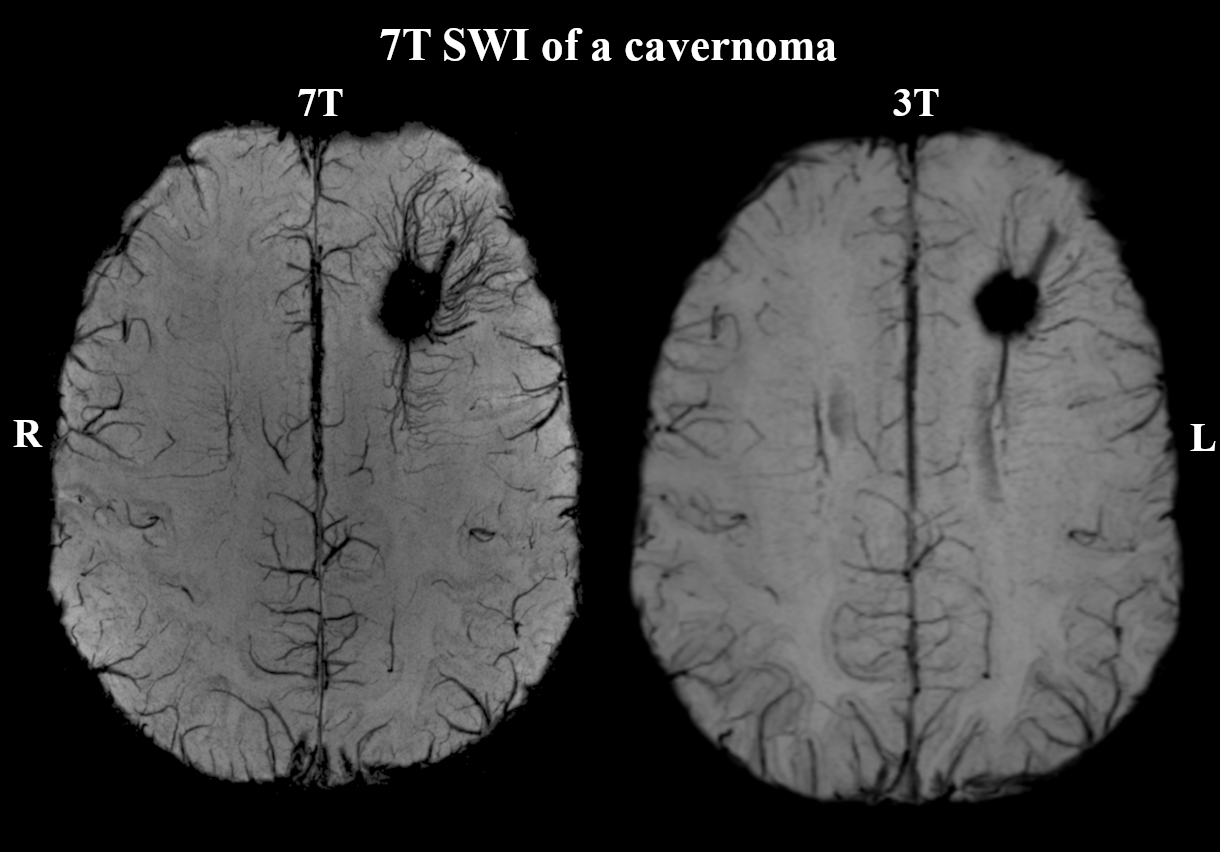

Additional 7T findings in 3T MRN patients were hippocampal abnormalities (three cases, examples in Figures 2+3) and focal cortical dysplasia (FCD) in one case, making up 19% of 3T MRN cases. 88% of the 17 patients with clinical 3T findings showed better delineation at 7T, as demonstrated for an FCD in Figure 4 and a cavernoma in Figure 5. Overall, in 50% of patients, potentially surgery-relevant information (e.g. additional findings or increased detail of known lesions) was found. B1+ inhomogeneities in the right temporal lobe were visible in all patients.

Figure 5: Example of 7T SWI’s enhanced imaging of vessels compared to 3T in skull-stripped transversal images of patient #27. There is a clear increase of detail in the delineation of the DVA surrounding the cavernoma.